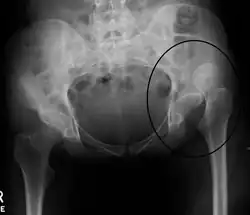

| X-ray showing a joint dislocation of the left hip. | |

An anterior-posterior (AP) X-ray of the pelvis and a cross-table lateral X-ray[24] of the effected hip are ordered for diagnosis.[4][5][16] The size of the head of the femur is then compared across both sides of the pelvis. The affected femoral head will appear larger if the dislocation is anterior, and smaller if posterior.[7] A CT scan may also be ordered to clarify the fracture pattern.[20]